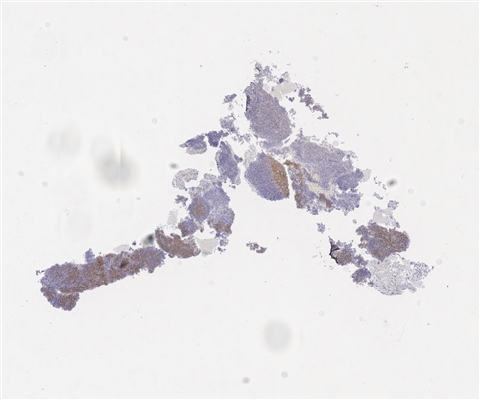

案例3 (7164)

性别:       年龄:19

患者详情: 发现颌下肿块1月,B超检查示颌下腺区域异常低回声,未见淋巴门结构,大小42*23mm,内部见较丰富血流信号,造影均匀等增强,NHL待排。行肿块穿刺活检。全身检查无肿大淋巴结。

大体所见: 巨检:条索状碎组织0.7*0.3*0.1cm。

医院: 复旦大学附属华东医院